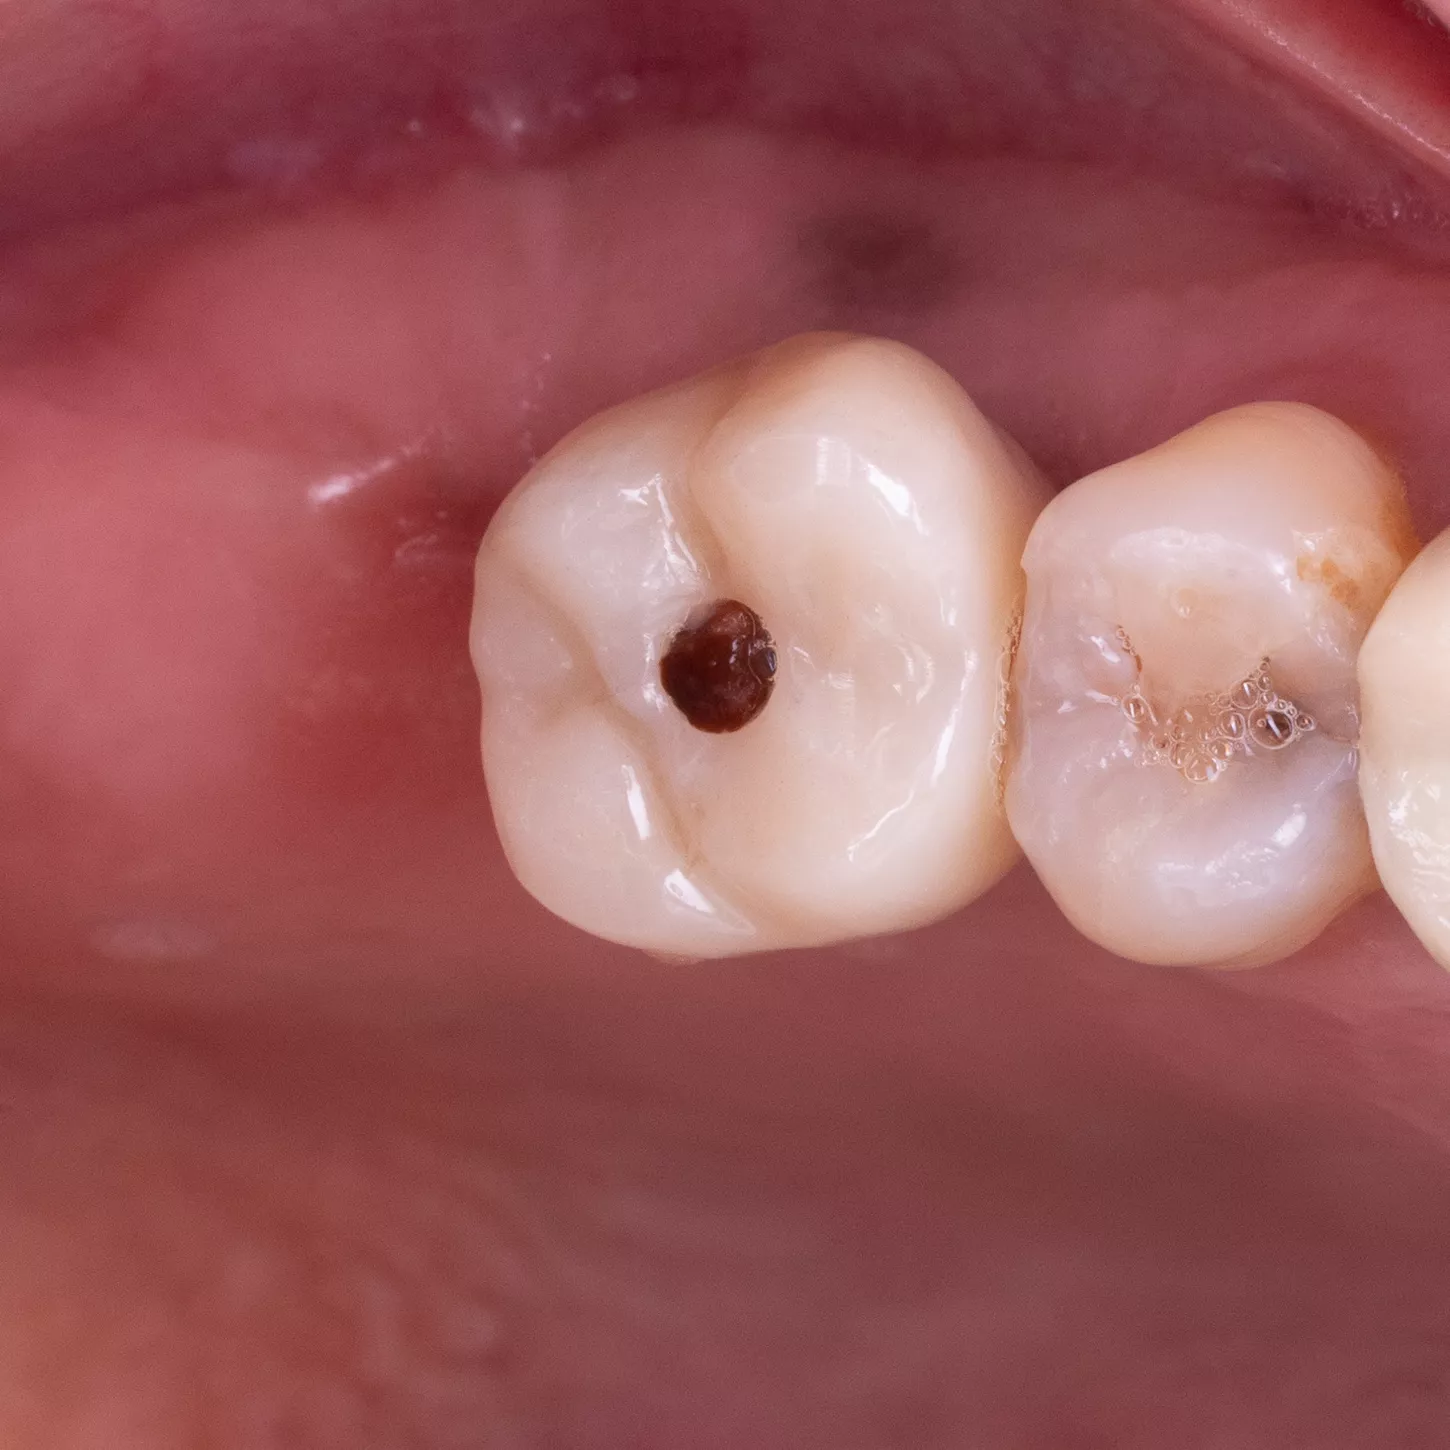

24. 25. 25. 27.

Clinical views of the implant-supported prosthesis 4 months after fitting. Lateral views in occlusion and occlusal views.